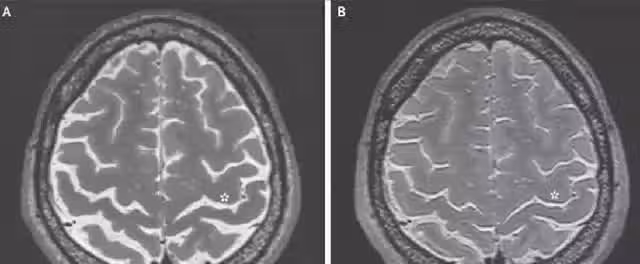

對於某些航天員的腦部檢查報告顯示,在他們返回地球後的一段時間裡,身體的健康狀況的恢復還是比較緩慢。對於一些太空人定期的檢查,發現了大腦腦脊液的分布變化,並沒有回歸正常。

因此有科學家認為,長期處於太空失重環境下,太空人大腦發生病變的幾率也會增大。